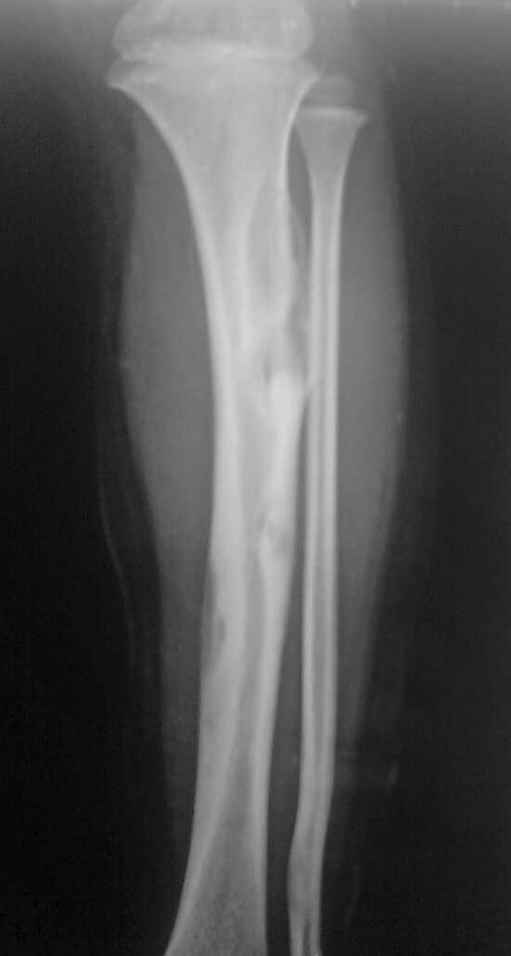

女孩4岁,左小腿肿物1年余,无痛,有跛行。胫前有肿物,质硬,无压痛。

胫骨增粗膨大,弯曲变形,多处骨皮质见囊性破坏,且呈纵轴发展,与正常骨分界欠清,破坏区内见高密度影。腓骨也累及。考虑骨纤,其他骨病变不排外。

胫骨增粗膨大,弯曲变形,多处骨皮质见囊性破坏,且呈纵轴发展,与正常骨分界欠清,破坏区内见高密度影。腓骨也累及。考虑骨纤,